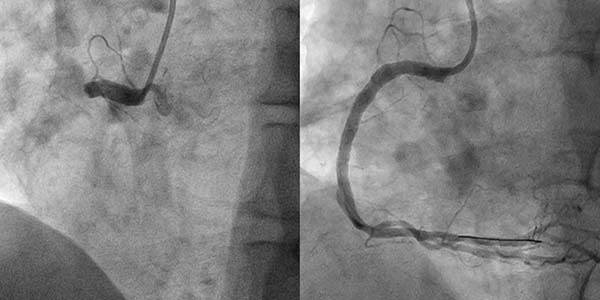

案例3

尹先生于2025年9月7日因结肠癌就诊于清华大学附属垂杨柳医院普外科,拟行结肠癌根治术。之前5年前曾因心绞痛于清华大学附属垂杨柳医院心内科行冠脉支架置入术。术前评估完善了冠脉CTA检查,结果提示:冠脉多发重度狭窄。遂由普外科转入心内科行冠脉造影提示患者回旋支、右冠脉重度狭窄,同期分别置入新型药物涂层支架,从心内科出院后1个月在普外科病房完成结肠癌手术。